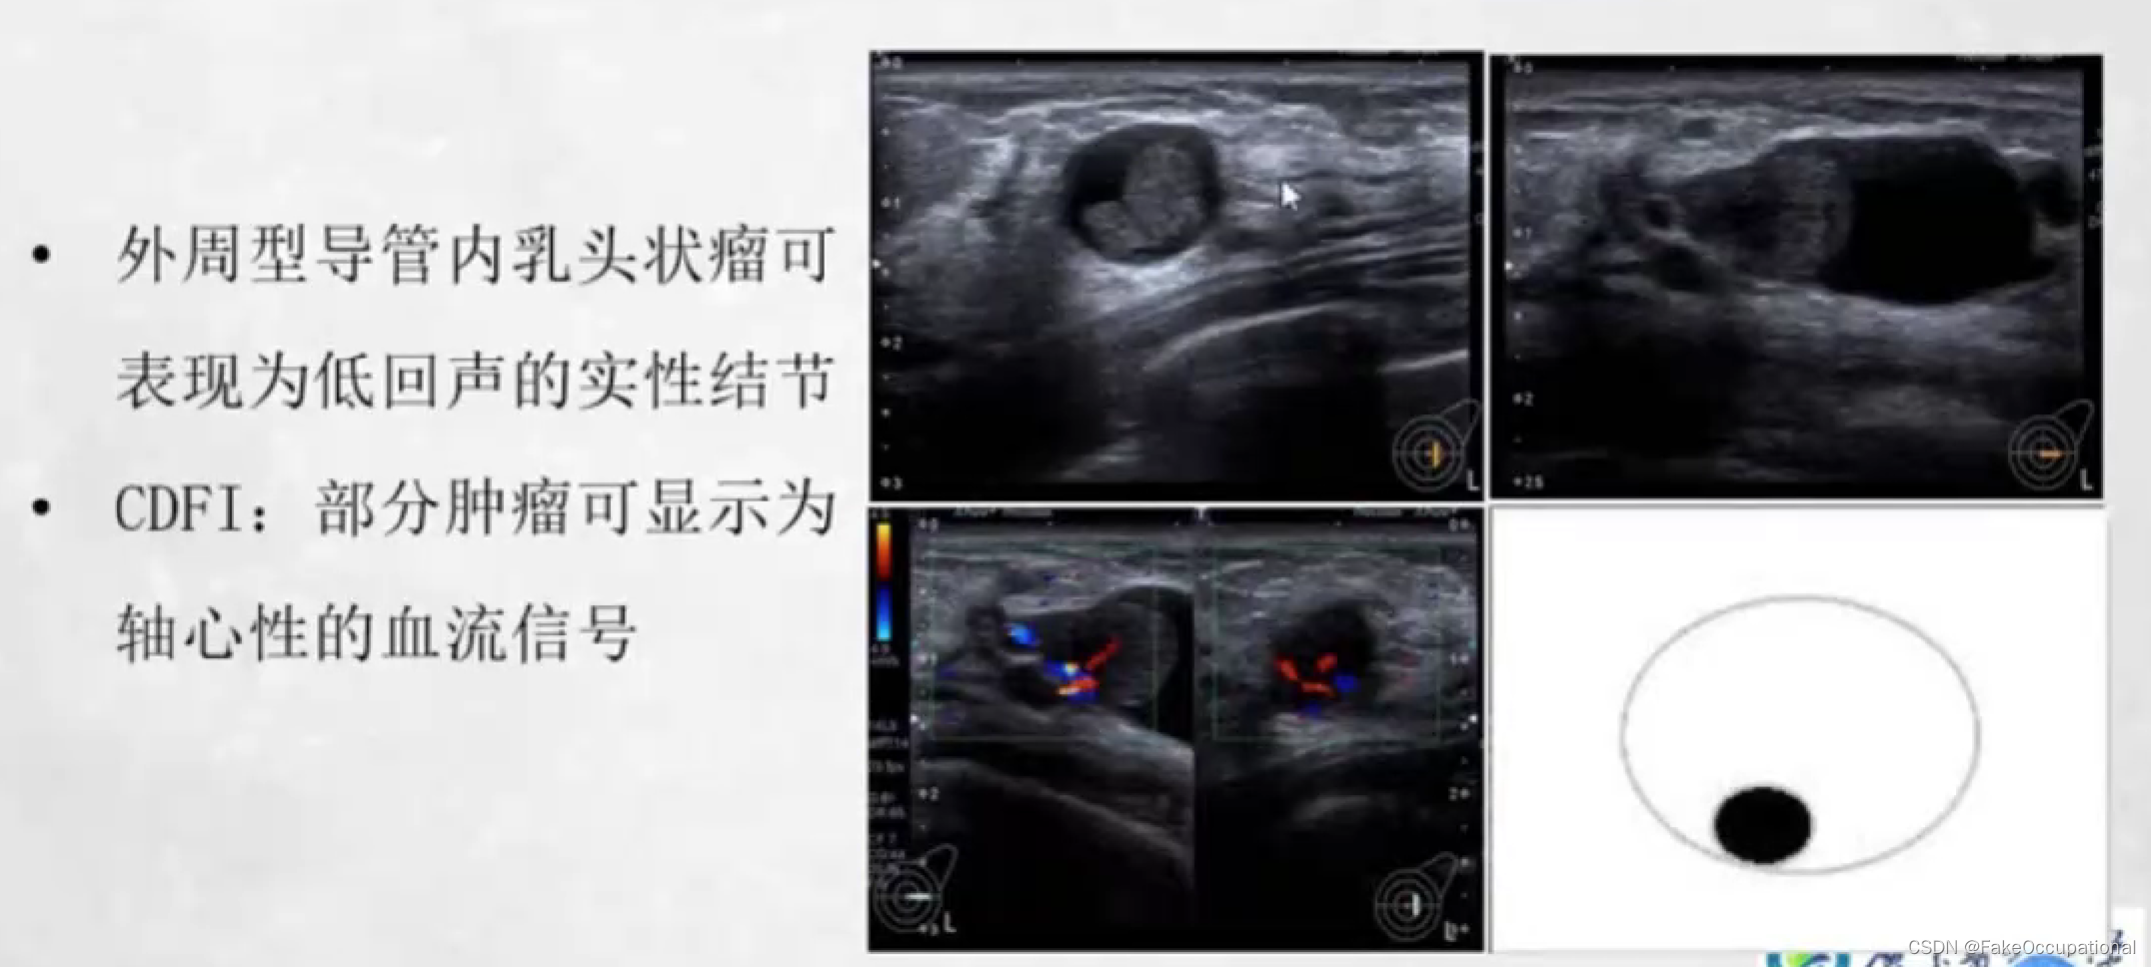

乳腺导管内乳头状瘤